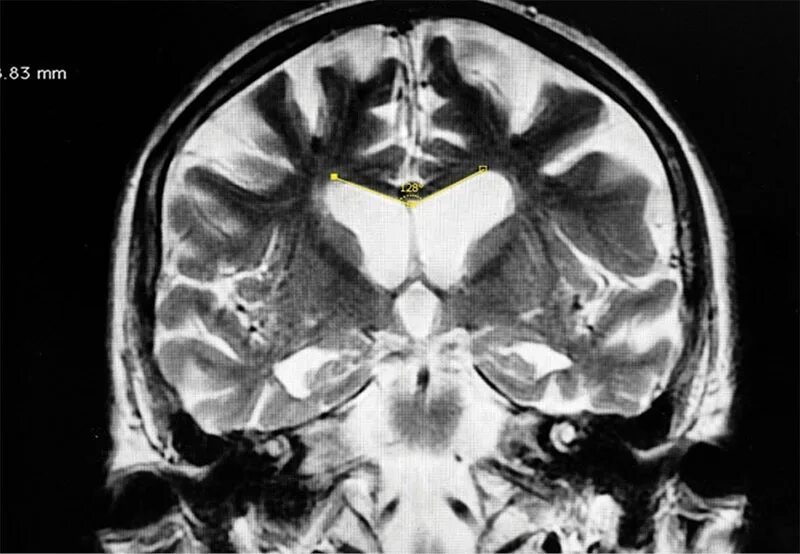

Расширение ликворосодержащих пространств